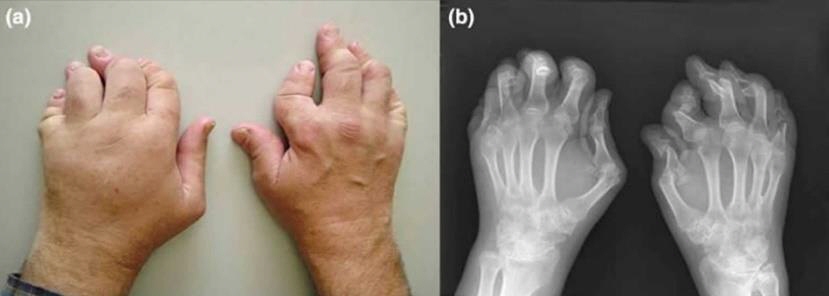

Left: PsA affected hands,causing severely damaged and deformed joints, Right: XRay of affected hands

Photos retrieved from Health Jade